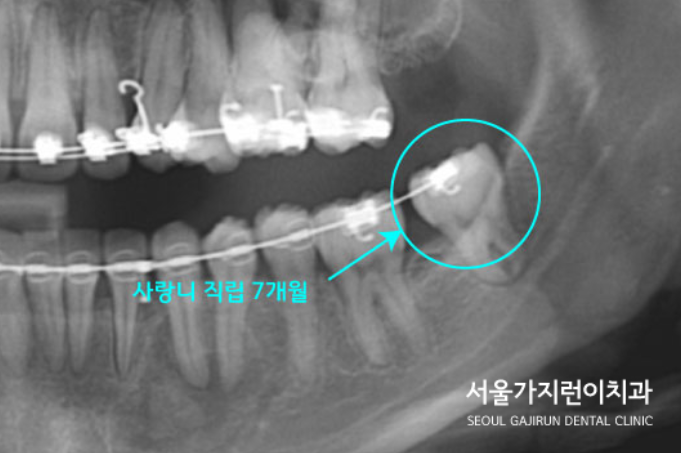

본원에서는 MBC 스프링 교정방식으로 사랑니를 서서히 세웠는데요.

7개월 정도 지났을 때 직립된 모습을 확인할 수 있었습니다.